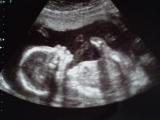

Ciąża - Brzuszki 29-32 tydzień - Zdjęcia